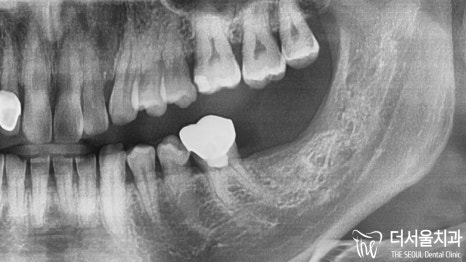

* 파노라마

좀 더 자세히 살펴보기 위해

엑스레이 촬영을 진행했습니다.

안 좋은 예감은 빗나간 적이 없네요.

육안 관찰을 했을 때도

약간 검게 물들어 있는 것을

확인할 수 있었는데요.

혹시!?나 싶었지만

역시였습니다.

옆으로 누워서 자란 사랑니 때문에

충치 가 생겨 있었는데요.

꽤 넓은 부위에 퍼져있었으며

앞에 있는 어금니 뿌리에도 영향을 끼치고 있었습니다.

파노라마에서만 봐도

충치 때문에 검게 변해있는 것을 관찰할 수 있네요.

제가 그렇게 검진을 강조 드리는 이유입니다.

미리 알았더라면..

인접치 병소는 막을 수 있었을 텐데요.